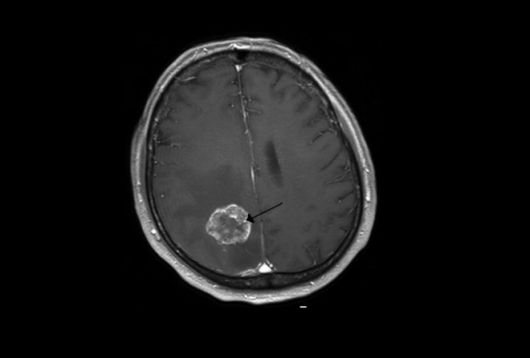

뇌종양 관련 이미지. 기사와 직접적인 관련 없음. 위키피디아 |

그러나 문제의 원인은 심리적인 것이 아닌 생물학적인 원인이었다. CT 검사를 받은 결과 그의 뇌에서는 7.5×8.1cm 크기의 종양이 발견됐다. 의료진은 그에게 3개월밖에 남지 않았을 수 있다며 시한부 진단을 내렸다.